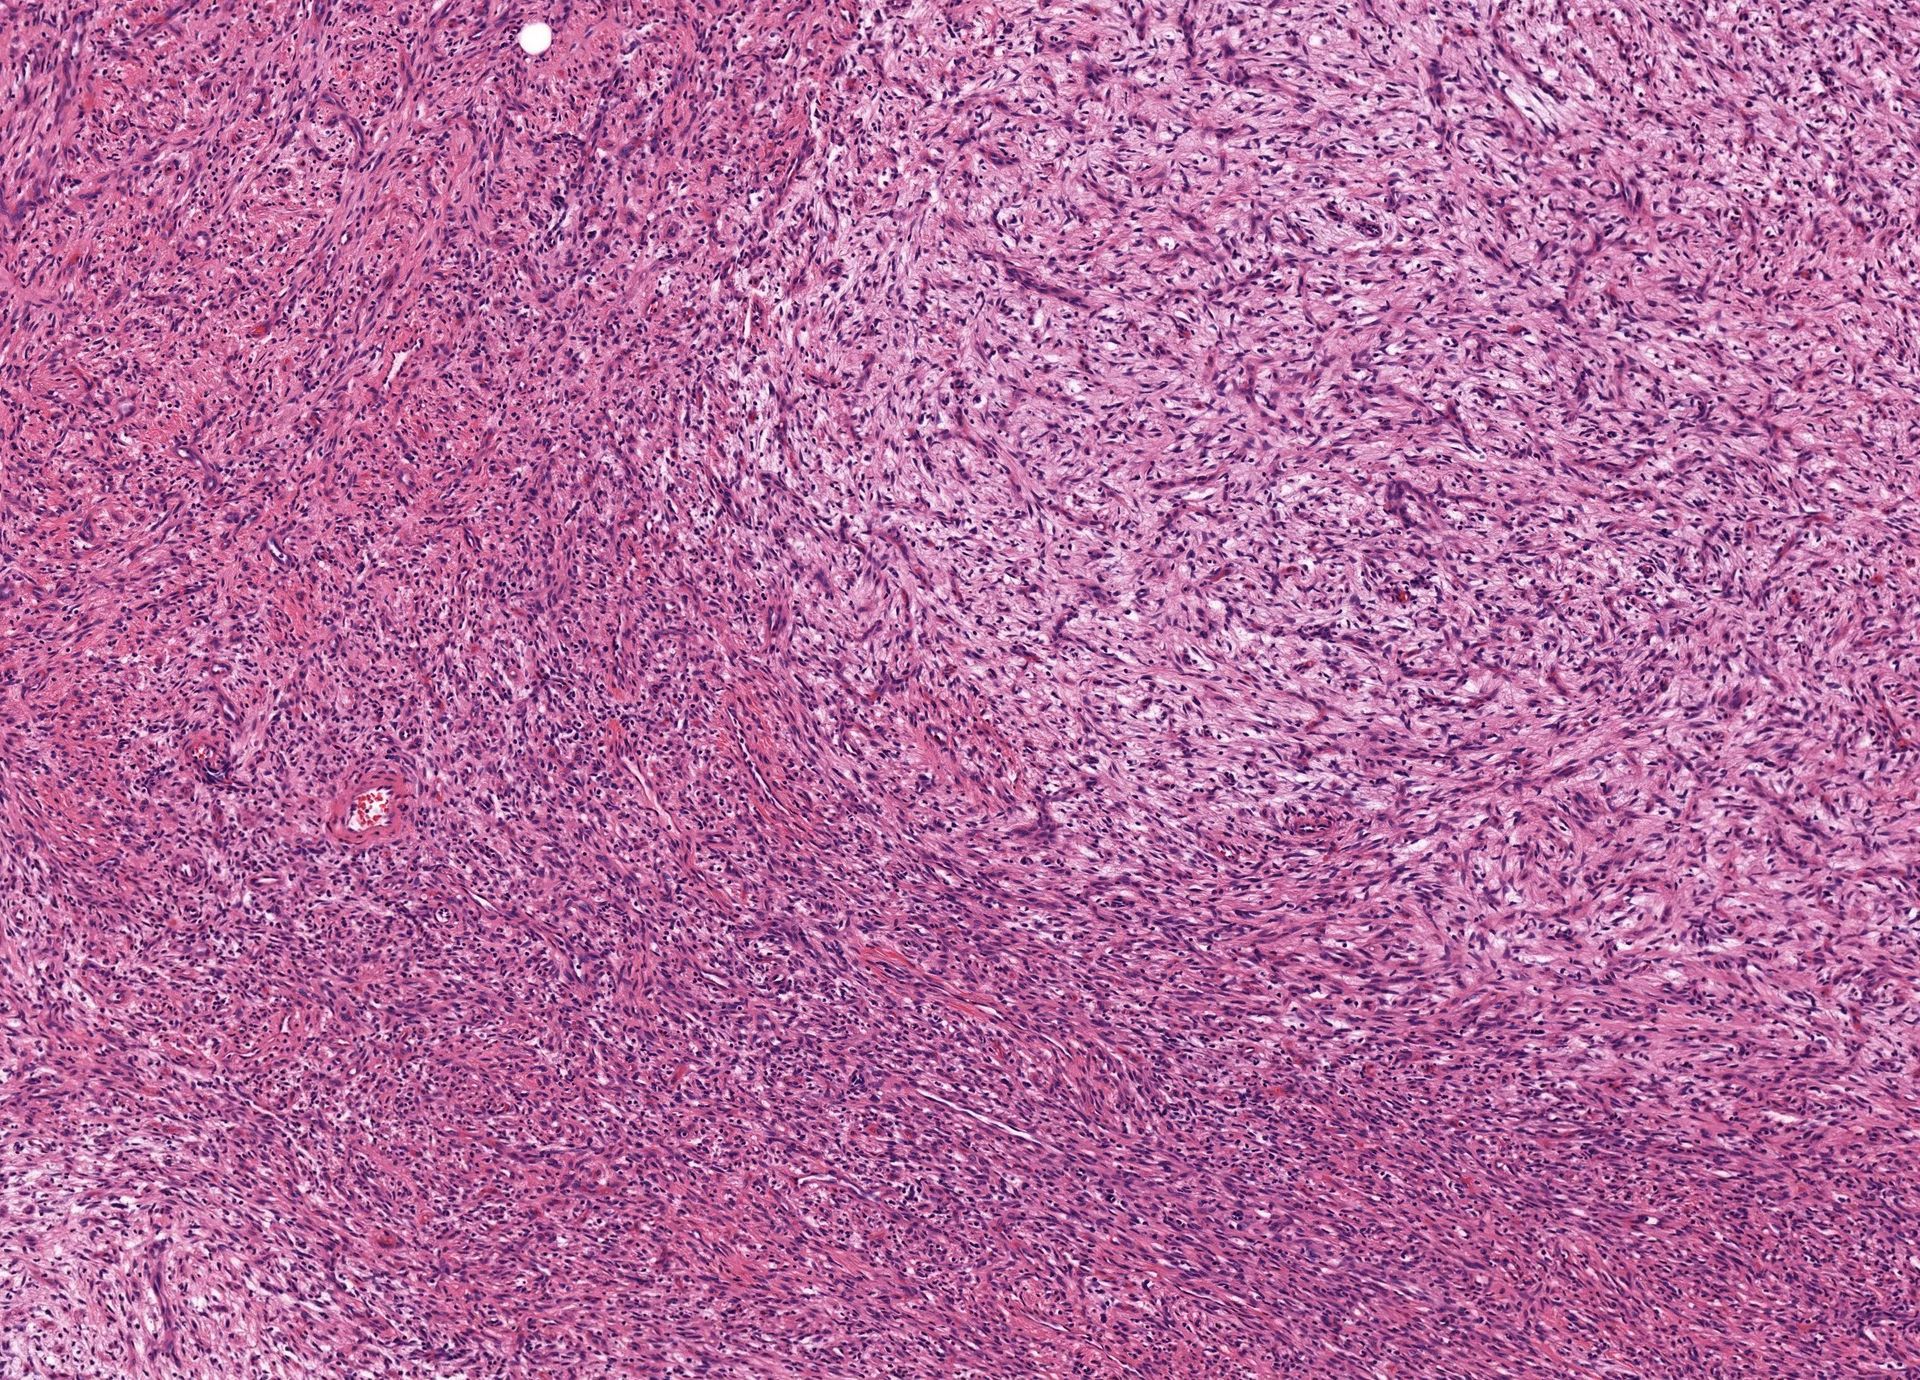

What process is happening here? How old is this patient?